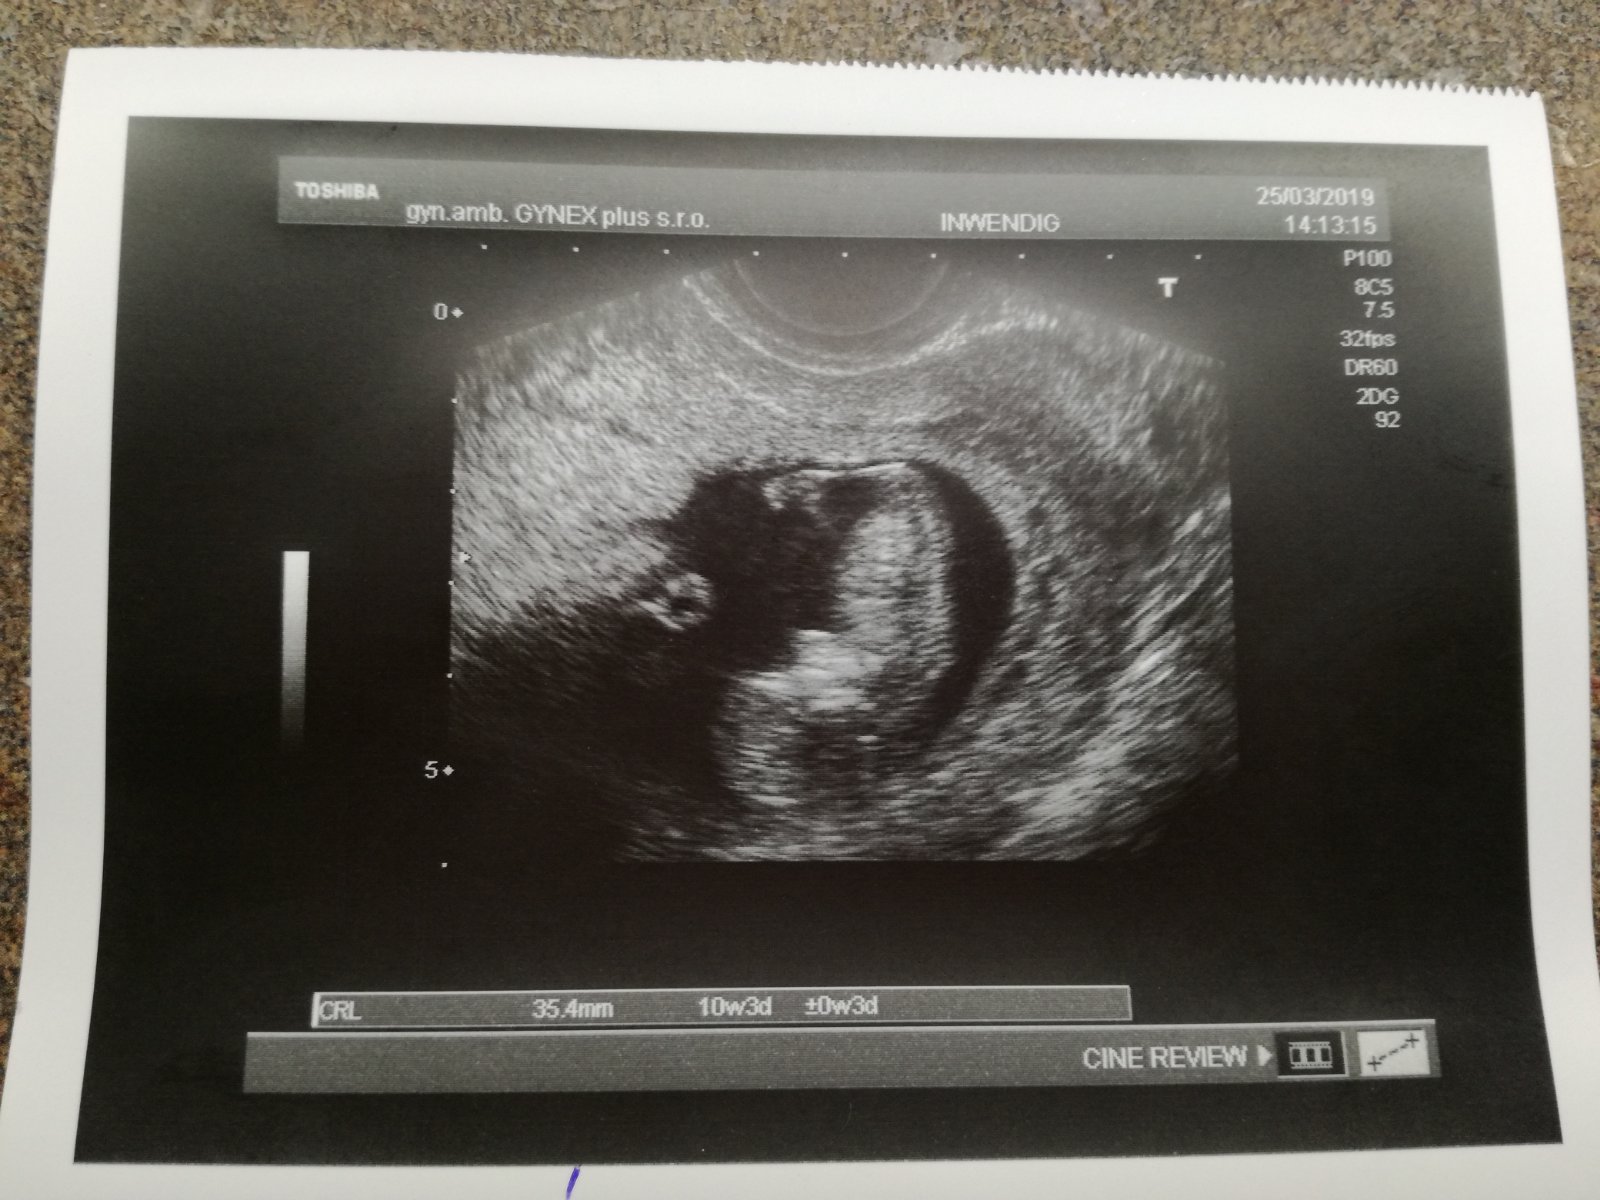

Ahoj holky. Tak já se šťastná hlásím. 🤗Dnes kontrola,všechno jak má být. Srdíčko bije,miminko má 3,5cm a jsem 11tt.😍Bylo nádherně vidět jak si tam plave.😊 Zítra si volám na screening. Snad bude všechno v pořádku i tam.🙏

Včera jsem zapomněla přidat foto.🙂